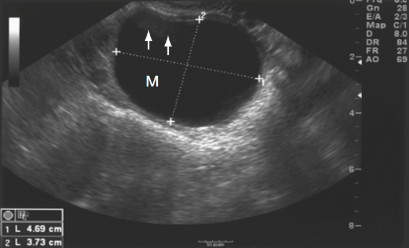

What is this an image of? And how do you know?

Complex cyst bc there are multiple loculations/compartments